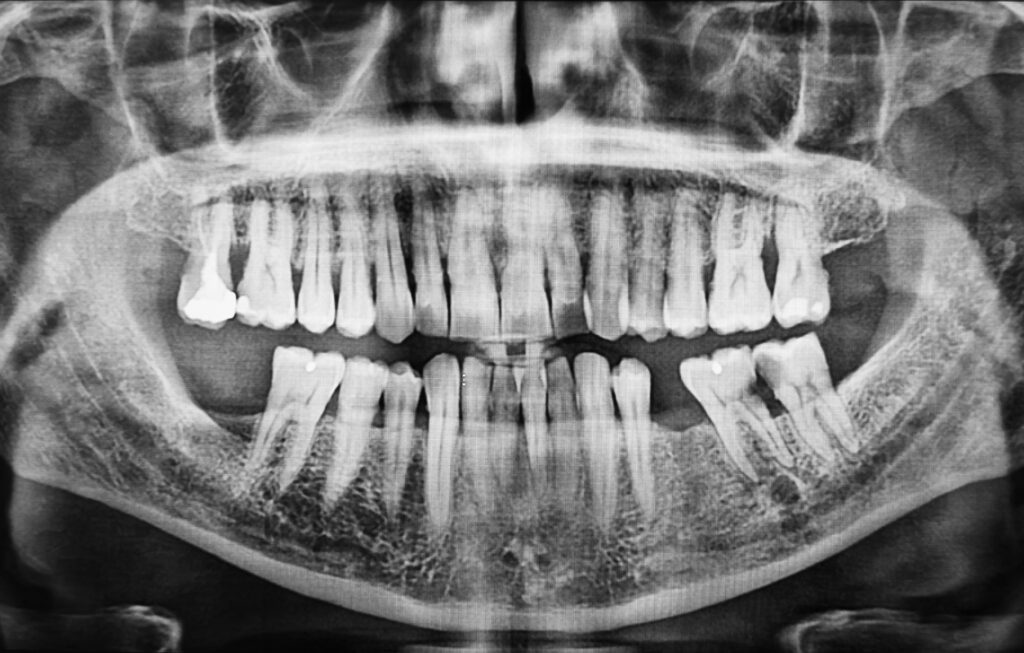

Can I Do Dental Implants Without Taking CBCT Scans or X-rays?

If you are considering dental implants, you may have been told that you need to take CBCT scans or dental X-rays before the procedure. It is not uncommon for patients to wonder: Is this really necessary? Can’t I skip the scans and just go straight to treatment? Is the dentist trying to fleece me? It […]